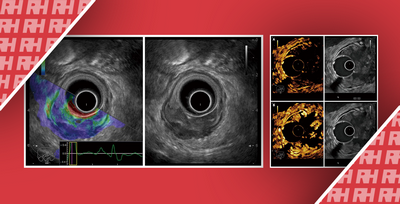

Новые методы визуализации влияют на диагностику заболеваний пищеварительной системы

Последние достижения в области колоноскопических технологий отражены в ряде исследований, представленных на Ежегодном научном собрании Американского колледжа гастроэнтерологии на этой неделе. В этом исследовании некоторые технологии лучше других позволяют улучшить обнаружение потенциально предраковых образований в толстой кишке, известных как аденомы. …